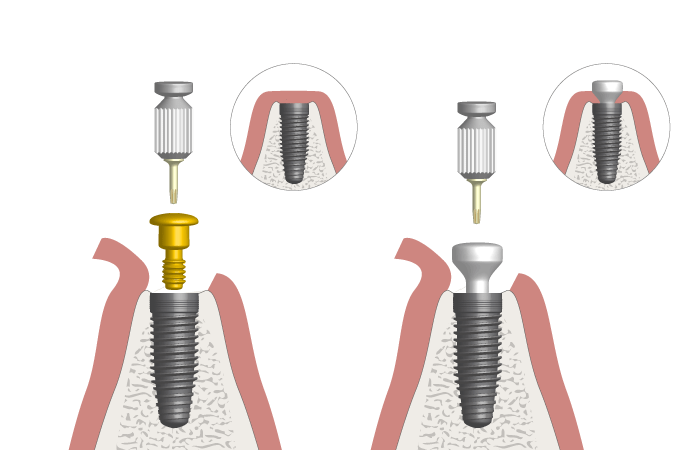

Consiste en exponer los implantes después de su integración ósea y colocar los pilares que servirán de soporte para las prótesis definitivas.

Cirugía de Conexión de implantes

Colocación de un pilar provisional para mantener el espacio y la estética mientras se espera la fabricación de la prótesis definitiva.

Colocación de Pilar de Cicatrización